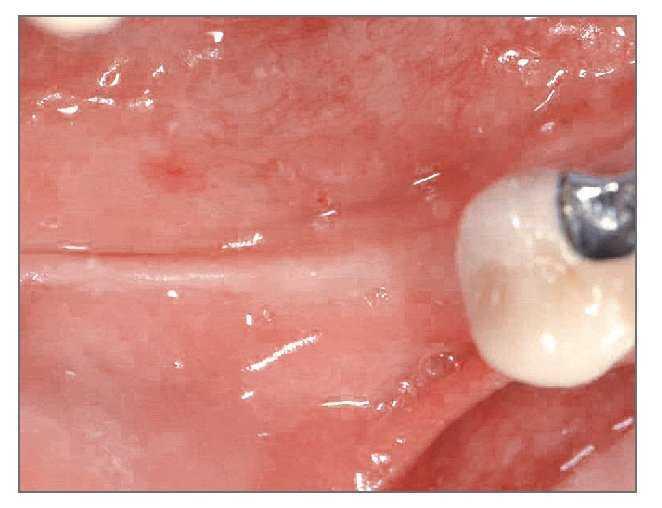

El paciente se enjuagó con colutorio de clorhexidina al 0,12% (Hexamedine, Bukwang) durante 2 min antes de la operación. Después de aplicar anestesia local con lidocaína al 2% y epinefrina 1:100.000, se levantó un colgajo de espesor total, poniendo de manifiesto el defecto óseo del alveolo vestibular. La dehiscencia vestibular era de 2,0 a 6,0 mm apicoronalmente. Se colocaron tres implantes de 3,8 x 12,0 mm (Implantium, Dentium) en el área molar de la mandíbula derecha con un torque de inserción de 40 Ncm (fig. 2). El defecto remanente y los vacios marginales se injertaron con hueso bovino deproteinizado (Bio-Oss, Geistlich Pharm) (fig. 3). Se empleó MDA para cubrir completamente el injerto óseo y asegurarlo bajo los colgajos vestibular y lingual (fig. 4). A continuación, se reposicionó el colgajo y se cerró la herida con suturas simples (Ethicon, Johnson & Johnson Medical).

Figura 2 (centro). Se colocaron tres implantes de 3,8 x 12,0 mm en el sextante mandibular derecho con un torque de inserción de 40 Ncm.